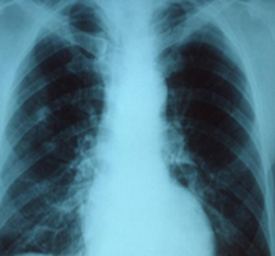

Post a description of what you see in your assigned patient x-ray.

Post a description of what you see in your assigned patient x-ray. Then, explain whether the patient has an enlarged heart, enlarged blood vessels, fluid in the lungs, and/or pneumonia in the lungs.